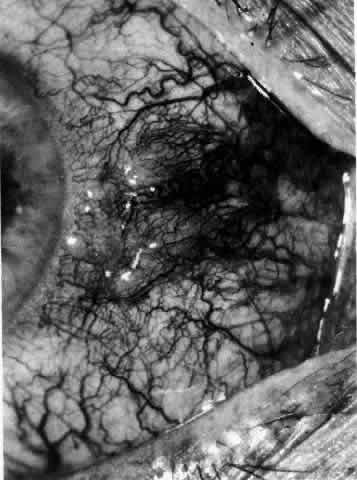

correct prognosis determined. HISTORY Careful taking of the patient's history sometimes reveals the cause. In general, the more rapid the onset, the more readily treatable the condition, and, consequently, the better the prognosis. Most scleral disease is bilateral and recurrent, and the history of suggestive attacks in the other eye should be sought. Alteration in visual acuity always indicates corneal or deep-seated disease. Many eye diseases are relatively painless. However, pain is a prominent characteristic of scleral disease; it is often the pain, rather than the redness of the eye, that causes the patient to seek advice. The pain of deep-seated scleral disease is severe and boring in character. It often radiates to the forehead and brow and characteristically awakens the patient during the night. The pain in superficial conditions is localized to the eye. On direct questioning, approximately one fourth of patients with episcleral and scleral disease will complain of lacrimation or photophobia. This is not a major symptom and is, surprisingly, not correlated with the presence of keratitis or any particular type of scleral condition. Scleral disease can be a manifestation of disease of any system of the body; therefore, a routine inquiry should be made concerning the cardiovascular system for evidence of arteritis or hypertension; the respiratory system for evidence of tuberculosis or sarcoidosis; and the genitourinary system for evidence of renal tuberculosis or venereal disease. A very strong relationship exists between skeletal and scleral disease, and an attempt should be made to determine whether there is any suggestion of connective tissue disease (e.g., a history of general malaise, pains in multiple or single joints, pains in the back or in the neck, and the presence of morning stiffness). Skin disorders that accompany or precede the onset of scleral inflammation include herpes zoster, rosacea, psoriasis, and erythema nodosum or arteritis. No central nervous system disease appears to be associated with scleral disease. Many patients with episcleritis give a history of recent viral disease, hypersensitivity reactions, or contact with external irritants, particularly industrial solvents. A family history of atopy is occasionally found in patients with episcleritis. Because most therapy for inflammatory scleral disease is administered systemically and is immunosuppressive in type, a history of gastric ulceration is of major importance because it may affect the type and extent of the therapy that can be given. EYE EXAMINATION Failure of vision is insidious, and the visual acuity must be measured at frequent intervals during the course of the disease. The external examination of the eye in daylight must never be omitted. This examination is essential to distinguish the deep discoloration, the increased transparency, and the area of maximum edema in deep scleral disease. No other method gives so much information; tungsten or fluorescent light is not as effective as daylight. Areas of deep inflammation and the extent of the progression of scleral disease have been seen quite often in daylight but have been invisible when examined with the slit lamp. The object of slit lamp examination is to determine the depth and nature of scleral and episcleral conditions and the presence of corneal changes. The changes seen are drawn in the records. With the use of diffuse light with a neutral density filter, the vascular networks of both eyes are examined in detail to determine the layer in which the vessels show maximum congestion, the infiltration of episcleral tissues, and the edema of sclera, episclera, or subconjunctival space. Slit lamp examination is also used to ascertain the nature and depth of any corneal changes; the presence of scleral edema (for which it may be necessary to blanch the superficial tissues with epinephrine 1:1000 or phenylephrine 10%); the nature of any episcleral infiltration or mass; and the presence of cells in the anterior chamber or vitreous and posterior synechiae. The red-free (green) filter is extremely valuable in confirming the areas of maximum congestion and whether any areas are totally avascular. Because this is an important physical sign and is easily missed, examination in red-free light should be routinely performed. The green light brings the vessels into very sharp contrast with the background and enables the position of maximum inflammation to be determined with certainty. It also enables the paths and configurations of the vessels to be followed and will show lymphocytic infiltration of the episcleral tissue as yellow spots; this often indicates that the condition is more extensive than previously supposed (Fig. 8).